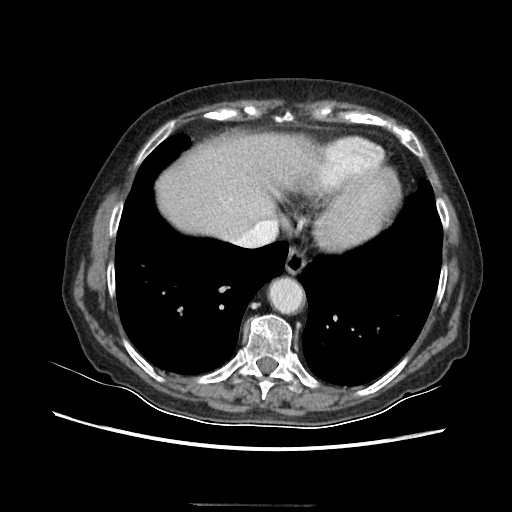

Original VENOUS CT scan

Full window (WL 1023.5, WW 4095 β†’ Low βˆ’1024, High +3071)

Mediastinum window (WL 40, WW 400 β†’ Low βˆ’160, High +240)

Targeted Slice 70 - Mediastinum Window Analysis (Generated vs Real Venous)

0.698

Mediastinum SSIM

58.6

Mediastinum RMSE

22.5

Mediastinum MAE